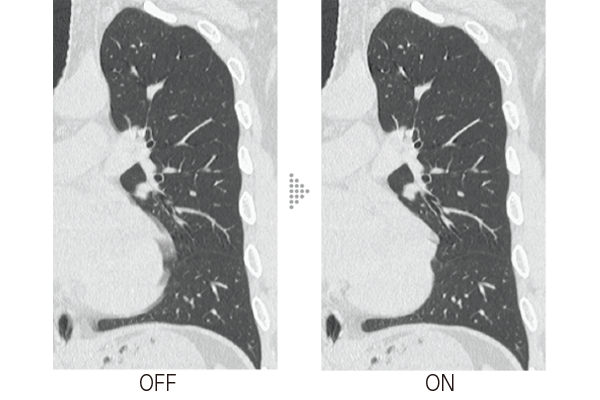

Intelli IPV is an image reconstruction technique developed with AI technology*3. Reconstruction processing has been speeded up by using images obtained through sufficient iterative processing as training data. Based on the Fujifilm's Visual Model, reconstruction processing using RawData brings the NPS(Noise Power Spectrum)closer to FBP(Filtered Back Projection)and keeps the image texture, even at a high noise reduction rate. It reduces image noise by up to 90%*4 and radiation exposure by up to 83%.*5 It also improves low contrast detectability by up to 2 times.*5

A technology to control image noise and image quality through iterative processing based on Statistical, Object, and Physics Models.

Modeled after FBP, adjusting texture in equal ratio from high to low frequencies while reducing noise to achieve a texture similar to that of FBP.

Models change in morphological information, and maintains structure considering shape, size, and position of the structure.

Reduces noise through statistical consideration of noise originating from X-ray detection and noise in circuit systems.

The noise frequency characteristics that affect visibility are now as close as possible to those of FBP while adjusting the texture in equal proportions from high to low frequencies.